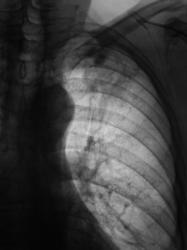

Пациент находится на диспансерном учете в туб. кабинете, по поводу инфильтративного туберкулёза верхней доли левого лёгкого, получает специфическое лечение. Пациент направлен в рентгеновский кабинет для рентгенологического исследования исследования органов грудной полости "в динамике". Проведено стандартное исследование.

Для сравнения приводятся изображения, произведенные чуть больше года тому.